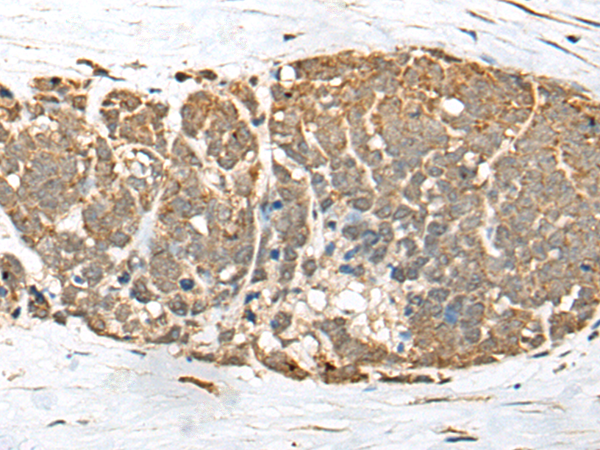

IHC positive control:

Human thyroid cancer

IHC Recommend dilution:

25-100